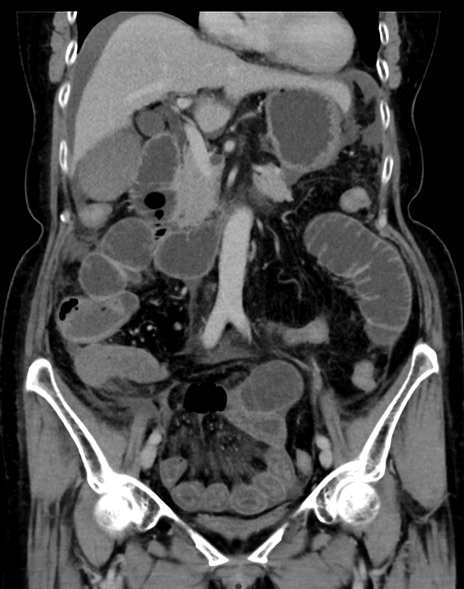

症例13 CT(冠状断像)1日半後

(横断像)1日半後